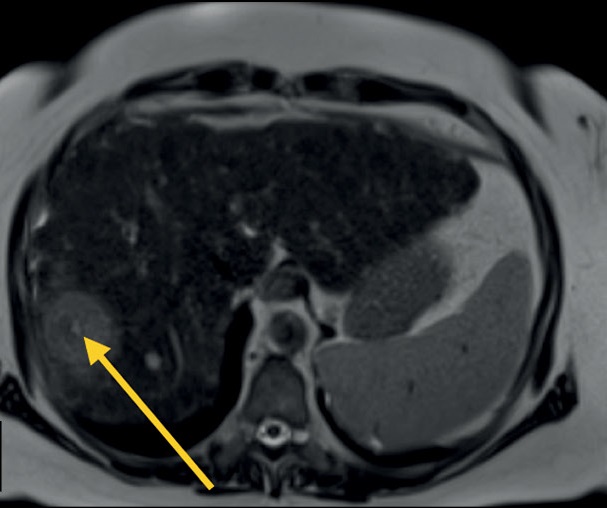

Основные импульсные последовательности в диагностике абдоминальной патологии

Магнитно-резонансная томография является одним из основных методов диагностики заболеваний органов брюшной полости и забрюшинного пространства, который позволяет с высокой диагностической точностью и воспроизводимостью визуализировать очаговые или диффузные изменения паренхиматозных и полых органов. Магнитно-резонансная томография имеет определённые преимущества перед компьютерной томографией в чувствительности и специфичности определения патологических изменений паренхиматозных органов, желчевыводящих путей и протоков поджелудочной железы, брюшины и органов забрюшинного пространства.

Мультипараметрический протокол сканирования предоставляет информацию не только о взаимной топографии органов и их структуре, но и о функциональном состоянии тканей, что позволяет перейти от структурной к функциональной оценке изображений. В большинстве случаев стандартный протокол включает сканирование органов брюшной полости (Т1-/Т2- и диффузионно-взвешенные режимы) и желчевыводящих протоков (магнитно-резонансная холангиопанкреатография), при этом данный протокол может быть значительно сокращён или дополнен в зависимости от целей исследования и состояния пациента.

Существующие технические разработки и достижения позволяют упростить процесс сканирования и сократить время на получение изображений, повышая при этом воспроизводимость методик в разных учреждениях здравоохранения.